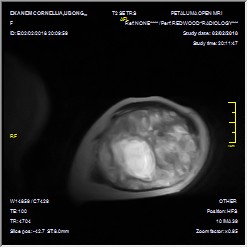

- Figure 3a_Axial MRI left arm

- Figure 3b. Coronal view MRI of the left arm